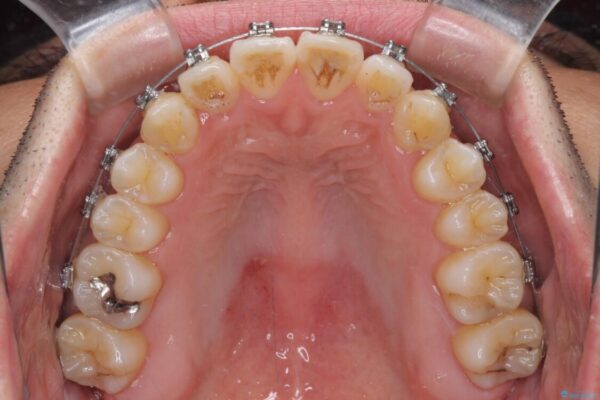

治療途中

• 左右の八重歯が気になる ワイヤー装置での咬み合わせ改善 治療途中画像